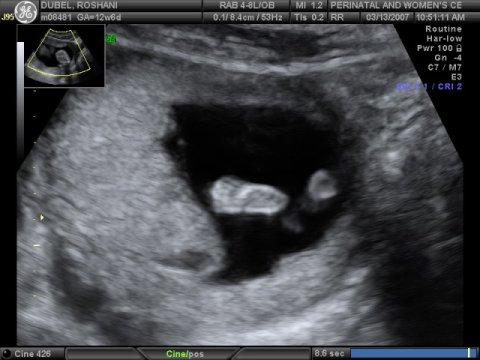

March 14, 2007

The

due date for Baby Miracle keeps changing. Original due date was

September 06, 2007, but an early ultrasound suggested September 19,

2007. Latest ultrasound, done on March 13, 2007, suggest that the

baby is expected to arrive September 09, 2007. It's still too

early to tell the sex of the baby but we should know by late

April/early May.

Tiny feet, tiny toes